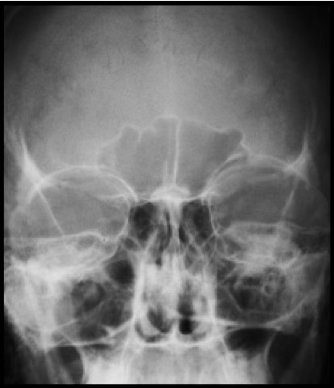

Waters

Waters part position

Chin on bucky, OML 37 degrees from IR

Waters central ray

Horizontal, exiting acanthion

Waters facial bones/orbits collimation

8x10